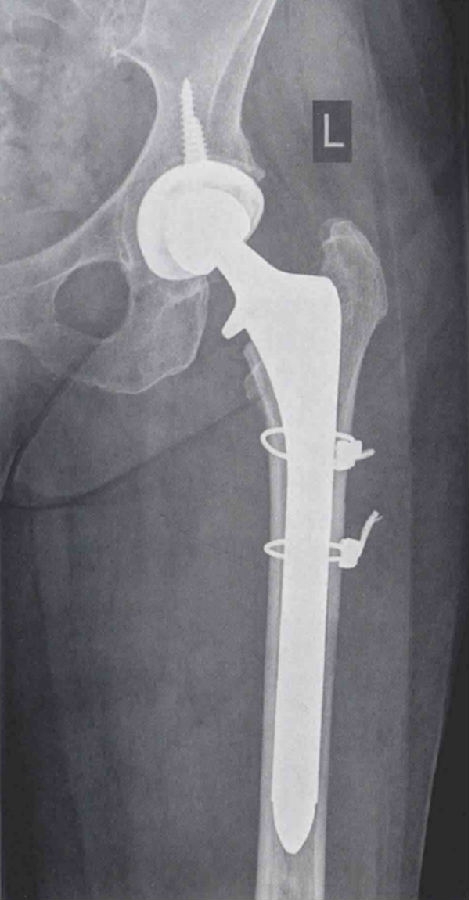

经过讨论后,我们决定对这名患者行左全髋关节翻修术。术前计划中我们拟使用远端固定型柄跨过骨折端,以达到良好的固定效果。

手术使用原切口,并稍向远端延长,以更好地显露近端股骨干。通过后侧入路显露髋关节并脱位,取下股骨头假体,然后仔细分离股外侧肌。在股骨近端发现一处轻微的无移位骨折。取出生物型柄后,使用两股钢丝捆扎复位骨折处。接下来处理股骨,为植入Echelon柄做准备。用铰刀依次从小号扩髓至17号。植入17号Echelon生物型柄后,检查股骨远端固定良好。复位后检查髋关节稳定性良好,下肢长度及偏心距得到充分恢复。

术后,患者可在完全负重下活动。术后X线片显示效果满意(图4和图5)。患者持续恢复良好。3个月随访中,患者完全无不适症状。

图4 左髋翻修术后正位X线片,使用远端固定型柄跨过骨折端,达到良好的远端固定效果1